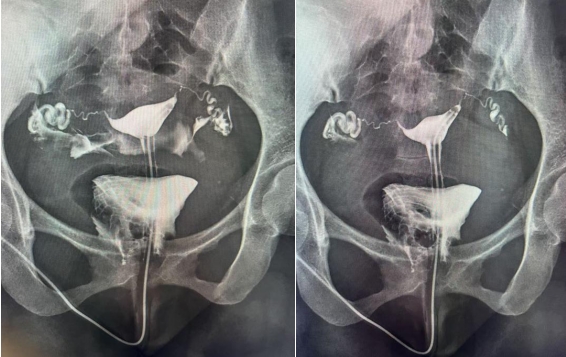

一、什么是子宮輸卵管造影?

子宮輸卵管造影是通過導(dǎo)管經(jīng)陰道、子宮頸向?qū)m腔及輸卵管內(nèi)注入造影劑,利用X線診斷儀透視并拍片,根據(jù)造影劑在子宮、輸卵管及盆腔內(nèi)的顯影情況,來了解和判斷子宮腔形態(tài),是否畸形、粘連,輸卵管是否通暢,以及輸卵管阻塞的部位。常用于不孕癥、輸卵管再通、子宮畸形等疾病的診治。如